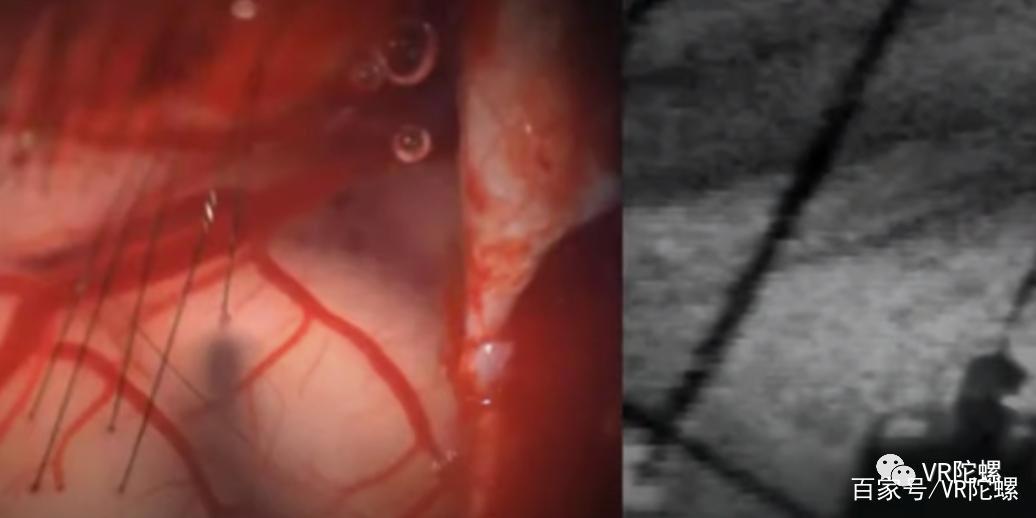

手术时,全自动的手术机器人会将一块硬币大小的头骨弄出来,然后将脑机接口放入大脑,最后用“超级胶水”一粘就可以了。马斯克称:“这项手术不会影响人的任何脑部组织,并且整个手术的过程只有一个小时,并且患者当天就可以出院。”

通过视频,我们看到脑机接口的传导线端口直接与大脑相连接,这相当于是在任何机器之间建立起了一个通信的桥梁。而至于这个桥梁能做什么,马斯克向我们展示了Neuralink在猪身上的几项最新实验成果。